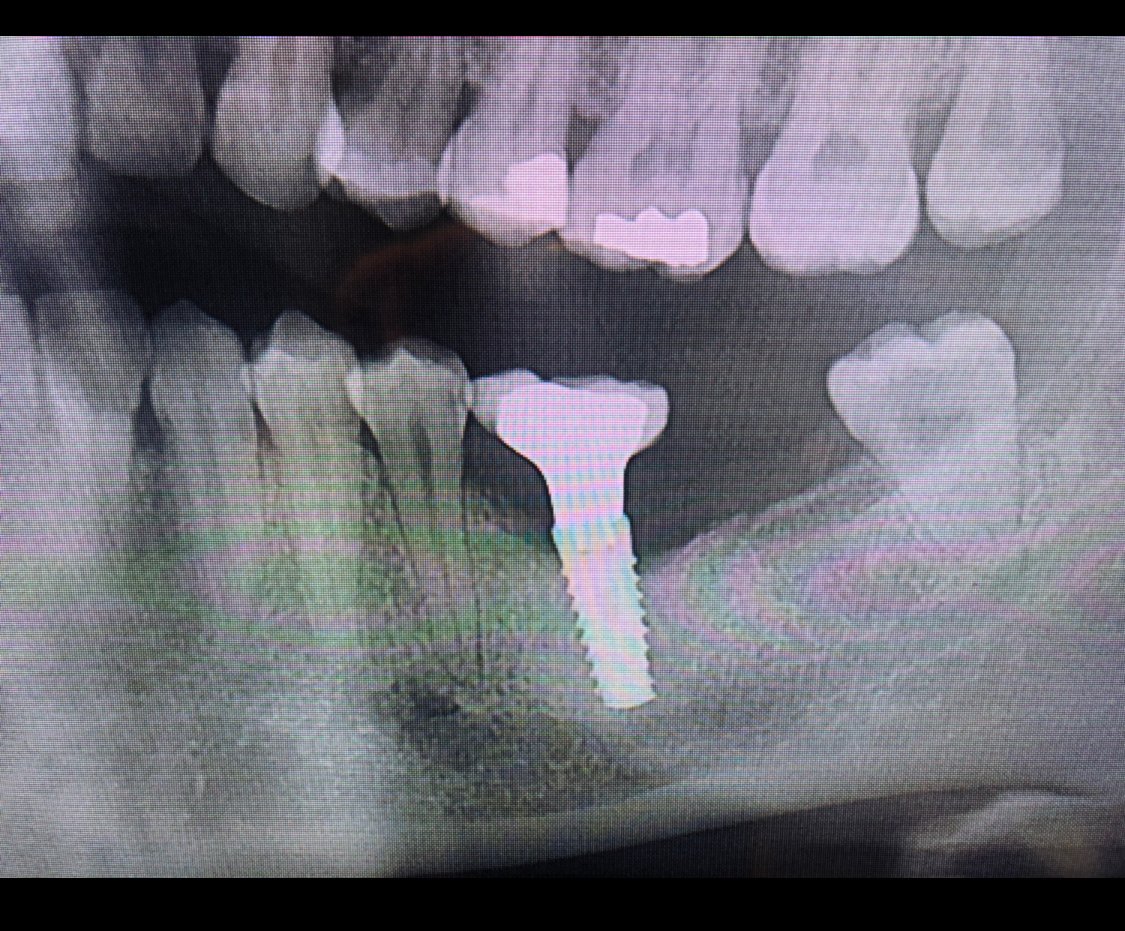

Este es el caso del Implante que quiero saber cual es pues la paciente no pudo darnos la información. El que he intentado subir ala plataforma y no me deja [...]

Buenos días. Estos casos que mando son de pacientes que vienen de una clínica que ha cerrado, y no se cuales son. Muchas gracias por su ayuda.

Abbiamo bisogno di conoscere la marca degli impianti nella foto in allegato per poter riprotesizzare.